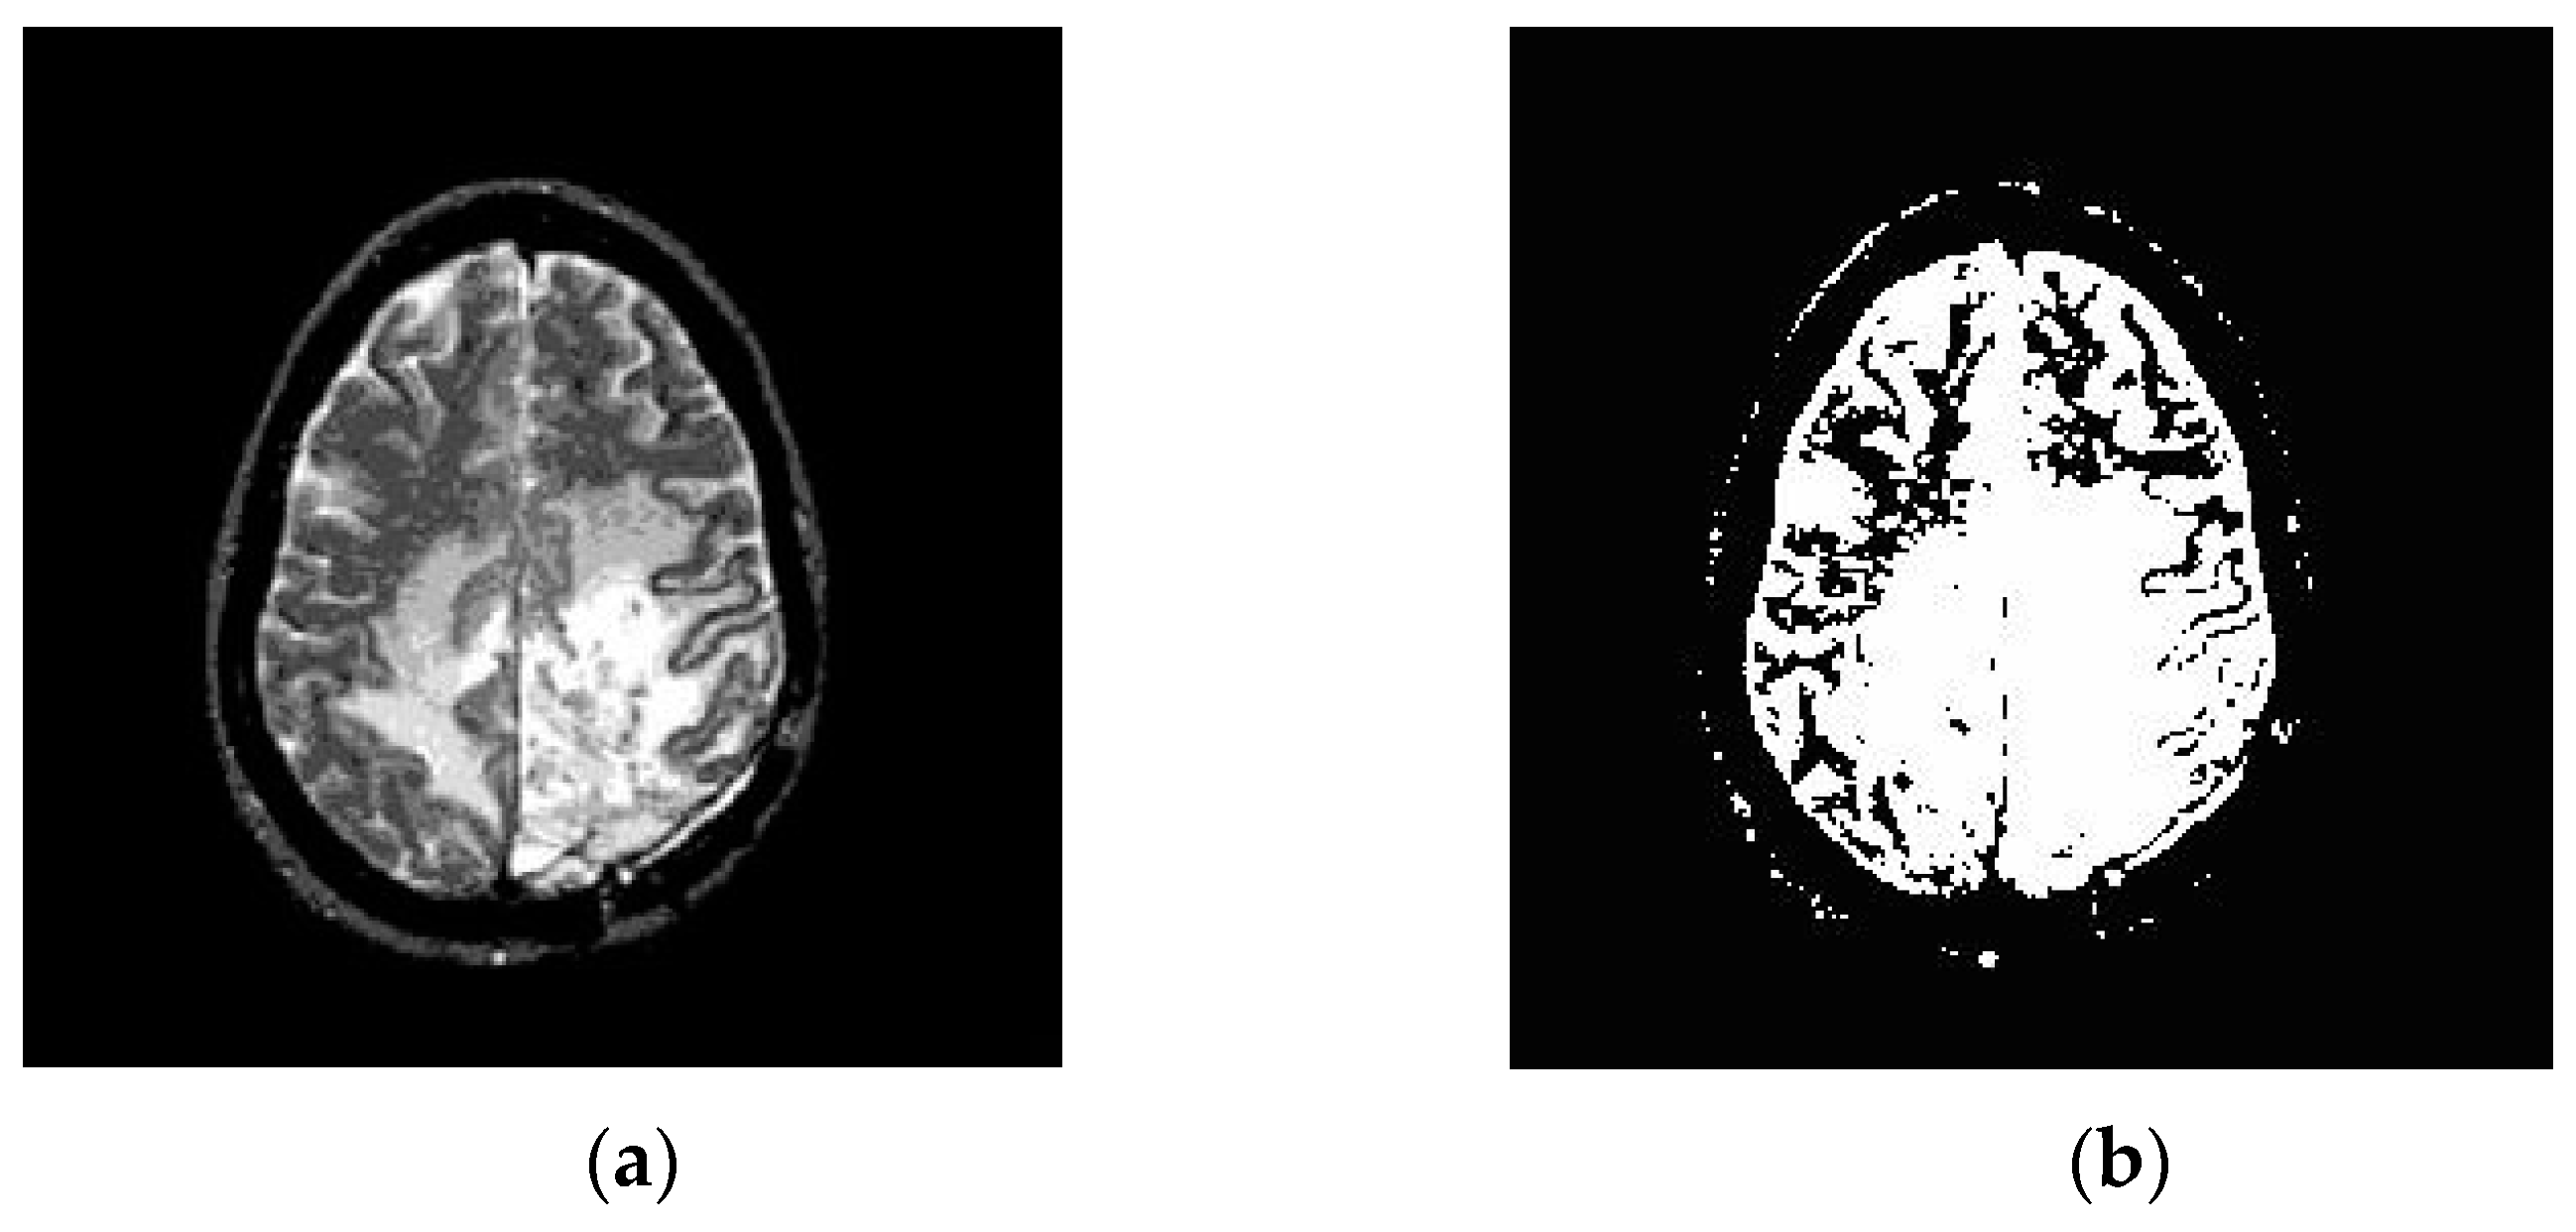

3.2. Segmentation

3.2.2. Fuzzy C-Means Clustering (FCM)